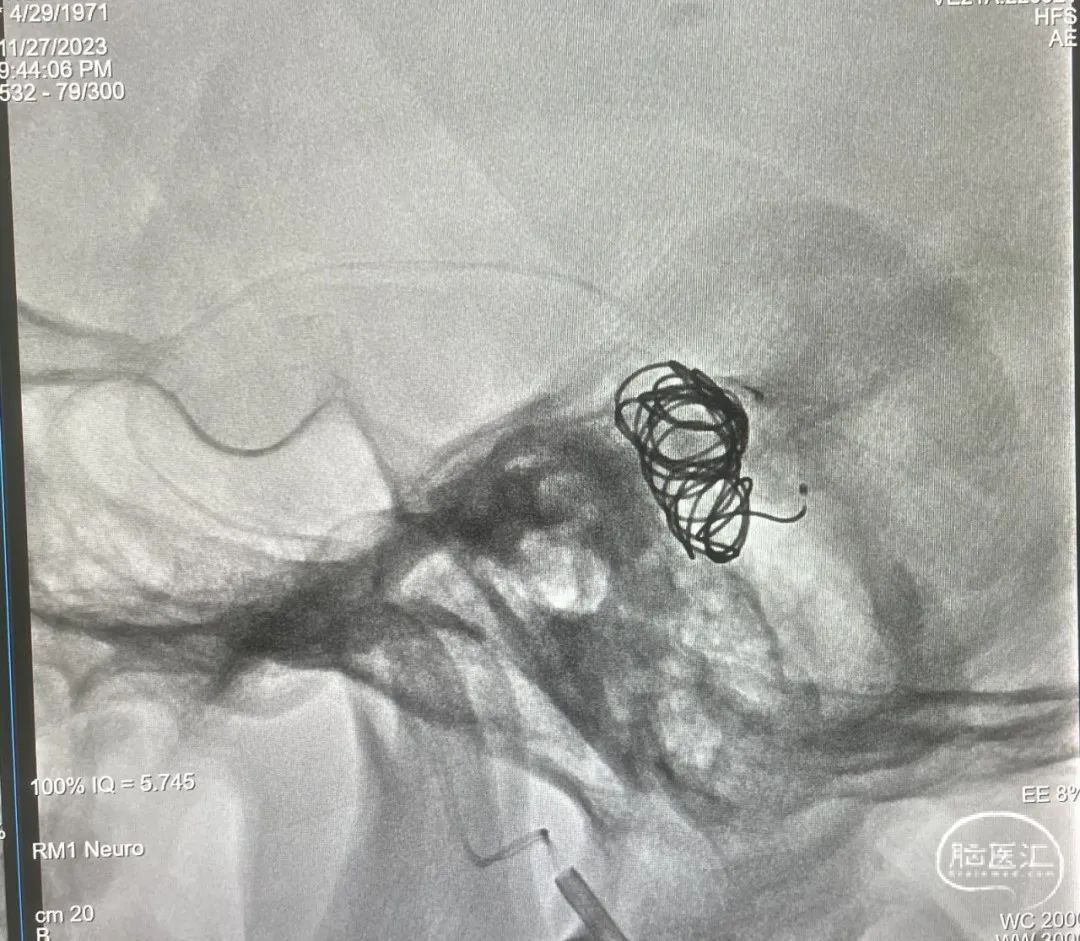

造影显示瘘口不显影,无静脉早显。

双侧颈外、颈内动脉正侧位造影瘘口均不显影

双侧椎动脉造影未见瘘口显影,可见广泛皮层静脉瘀滞

Onyx胶铸型显示瘘口形态。